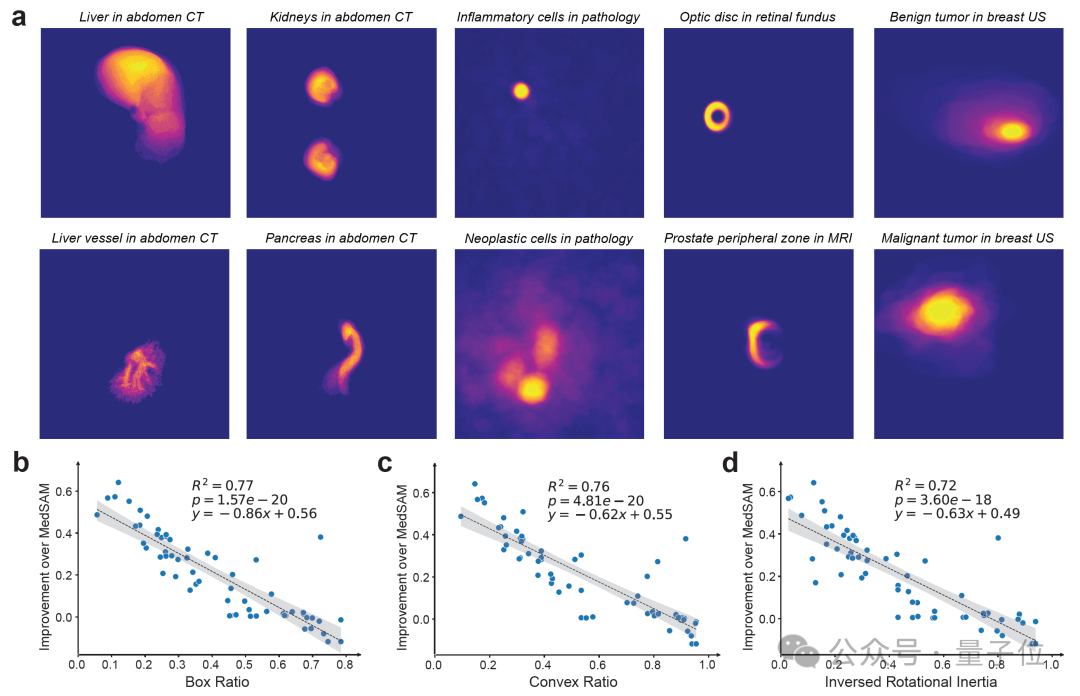

不仅复杂、不规则形状对象能高精度识别:

在分割不规则形状的生物医学对象方面,BiomedParse相较传统模型表现卓越。通过将图像区域与临床概念关联,相比手动框选分割精度提升39.6%,提高了在关键任务中的可靠性。

生物医学图像中的不规则对象一直是传统模型的难题,而BiomedParse通过联合对象识别和检测任务,通过文本理解实现了对对象特定形状的建模。对复杂对象的识别精度远超传统模型,且在多模态数据集中进一步凸显了其优势。